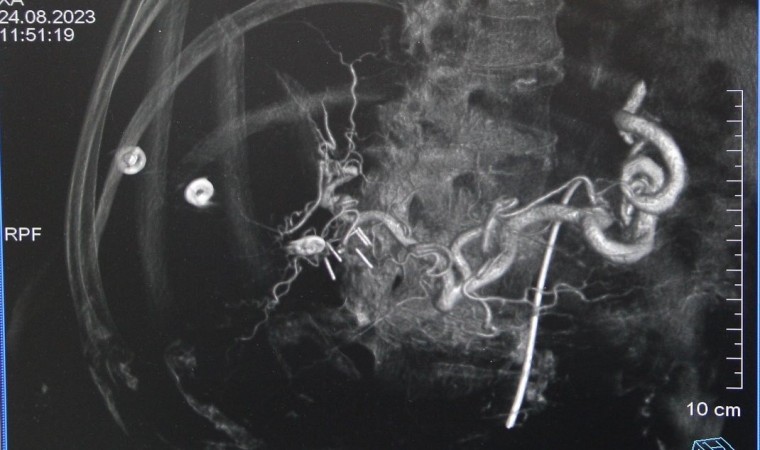

Kütahya Evliya Çelebi Eğitim ve Araştırma Hastanesi Girişimsel Radyoloji Hekimleri Prof. Dr. Mehmet Korkmaz ve Doç. Dr. Furkan Ertürk Urfalı tarafından, Kütahya’da ilk defa karaciğer tümörü olan üç hastaya Transarteriyel Radyoembolizasyon (TARE) işlemi gerçekleştirildi. Başarılı işlem sonrası Transarteriyel Radyoembolizasyon (TARE) hakkında bilgi veren Prof. Dr. Mehmet Korkmaz, ”Transarteriyel Radyoembolizasyon, karaciğer kanserlerini ve başka organ kanserlerinin karaciğere metastazlarını tedavi etmek için kullanılan bir tedavi yöntemidir. İçinde radyoaktif madde bulunan çok küçük boyuttaki kürelerin (mikroküre) direkt olarak kanser dokusu içine, kanser damarları yoluyla verilmesidir. Tümör ve metastazlarına yol açan hücrenin bulunduğu alana Nükleer Tıp uzmanlarımız tarafından hesaplanan dozlarla, radyoaktif madde içeren küçük küreciklerin (mikroküreler) enjekte edilmesidir. Radyoaktif madde olan itriyum-90 (Y90) mikroküreler, sağlıklı dokular korunarak, tam olarak tümör üzerine radyasyon uygulayarak etki ederler. Bu sayede çevre dokular zarar görmez. TARE tedavisi ile, karaciğerdeki tümörü küçülterek cerrahi tedaviye uygun hale gelmesini sağlar. Kanserli hücreleri öldürerek hastanın organ nakli için zaman kazanmasını sağlarken, organ nakli için başlangıçta uygun olmayan tümörü küçülterek nakil için imkan sağlar” dedi.

Prof. Dr. Korkmaz, ”TARE tedavisinde mikroküreler bir kan damarından geçer ve karaciğer tümörüne direkt ulaşır. Bu sayede radyoaktif madde, diğer radyasyon tedavilerinde olduğu gibi, kanser hücrelerine ulaşmak için vücudun sağlıklı kısımlarından geçmez. Doç. Dr. Furkan Ertürk Urfalı hocamız ve Nükleer Tıp Uzmanımız Dr. Elif Neslihan Akdemir’in destekleriyle birlikte hastanemizde ilk defa üç hastamıza, işlemi başarıyla gerçekleştirmiş bulunmaktayız. Bu işlemlerin yapılmasında emeği geçen ekibime ve bize bu imkanı sağlayan KSBÜ Rektörü Prof. Dr. Ahmet Tekin, İl Sağlık Müdürü Dr. Öğr. Üyesi Sertaş Erarslan ve Başhekim Dr. Öğr. Üyesi Serkan Telli’ye teşekkür ediyorum “ dedi.